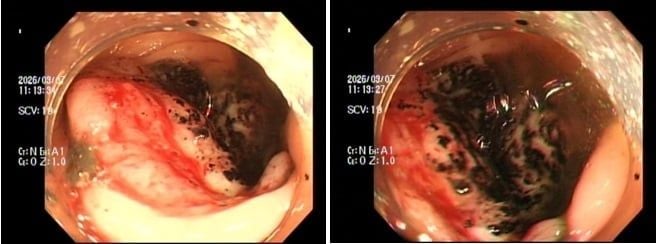

Trường hợp 1, chị P.V.P.U (sinh năm 1991) đến khám chỉ vì... ông xã thấy dạo này da dẻ chị quá xanh xao. Bản thân chị thỉnh thoảng cũng cảm thấy đôi lúc đau bụng nhẹ, nhưng lại tặc lưỡi bỏ qua vì nghĩ là rối loạn tiêu hóa thông thường. Khi thăm khám, bác sĩ phát hiện chị bị thiếu máu nặng. Ngay lập tức, chị được chỉ định nội soi đại tràng, kết quả khiến cả hai vợ chồng sững sờ: Có một khối u lớn ở đại tràng phải, bề mặt loét và rất dễ chảy máu, kết quả mô học khẳng định: Ung thư đại trực tràng.

Trường hợp 2, anh N.H.H.H (sinh năm 1995) đến viện với dáng vẻ mệt mỏi rã rời, than phiền hay bị chóng mặt kèm theo rối loạn đi cầu. Cứ nghĩ do làm việc quá sức, nhưng kết quả xét nghiệm lại báo động tình trạng thiếu máu nặng. Bác sĩ cho tiến hành nội soi đại trực tràng và phát hiện một khối u dạng vòng nhẫn đang chảy máu rỉ rả ở vùng trực tràng. Giải phẫu bệnh một lần nữa gọi tên: Ung thư trực tràng.

Hình ảnh nội soi đại tràng - Ảnh: BV